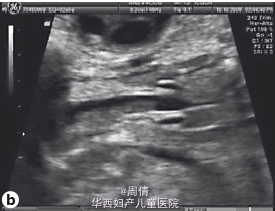

超声提示胎儿颈部冠状位正常的喉部和声带闭锁 胎儿颈部冠状位正常的喉部和声带图像 胎儿颈部冠状位正常的喉部和声带闭锁的图像